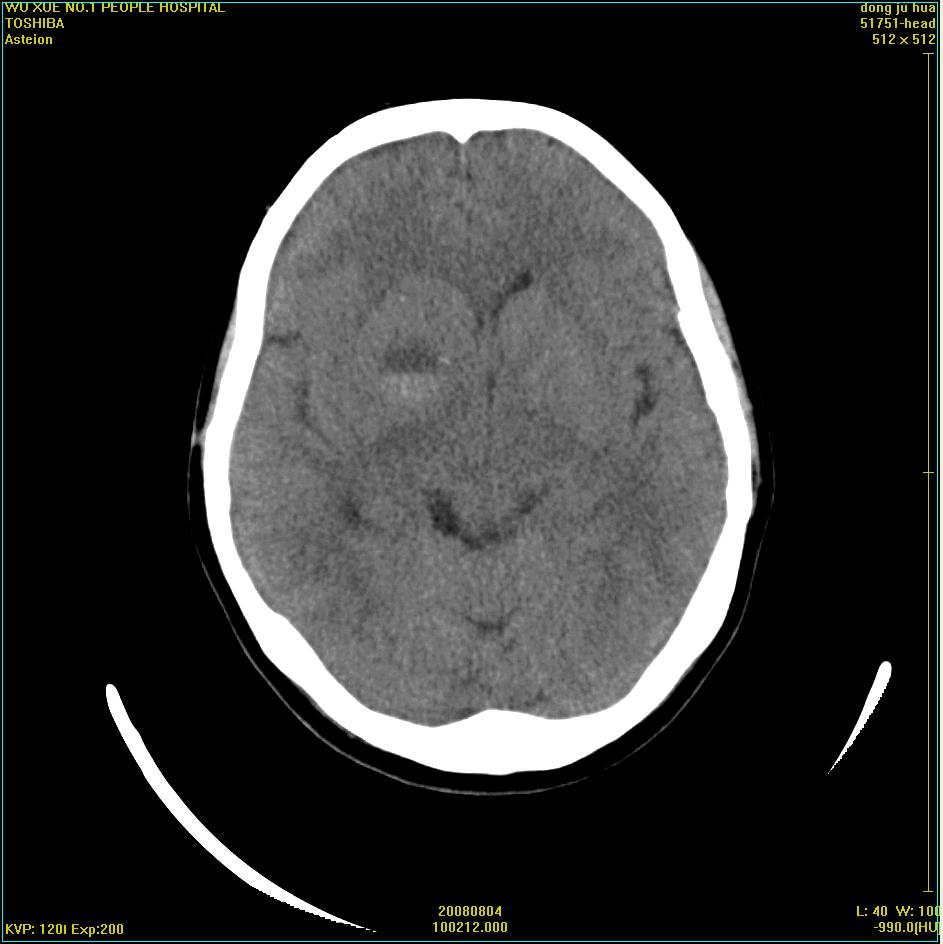

患者,女,45岁。四年前在我院做ct诊断为右侧桥小脑脚区三叉神经鞘膜瘤,已做手术。今复杳。请大家看看

三叉神经鞘膜瘤术后

考虑三叉神经鞘膜瘤术后复发并瘤体内出血。

三叉神经鞘膜瘤术后复发并瘤体内出血

考虑慢性扩张性血肿吧!请大家再看看,发表高见!

考虑:三叉神经鞘膜瘤术后复发并瘤体内出血。支持!

四年前做的手术,为什么大家不考虑慢性颅内血肿呢?

考虑慢性颅内血肿?症状体征有多少?能否发上?